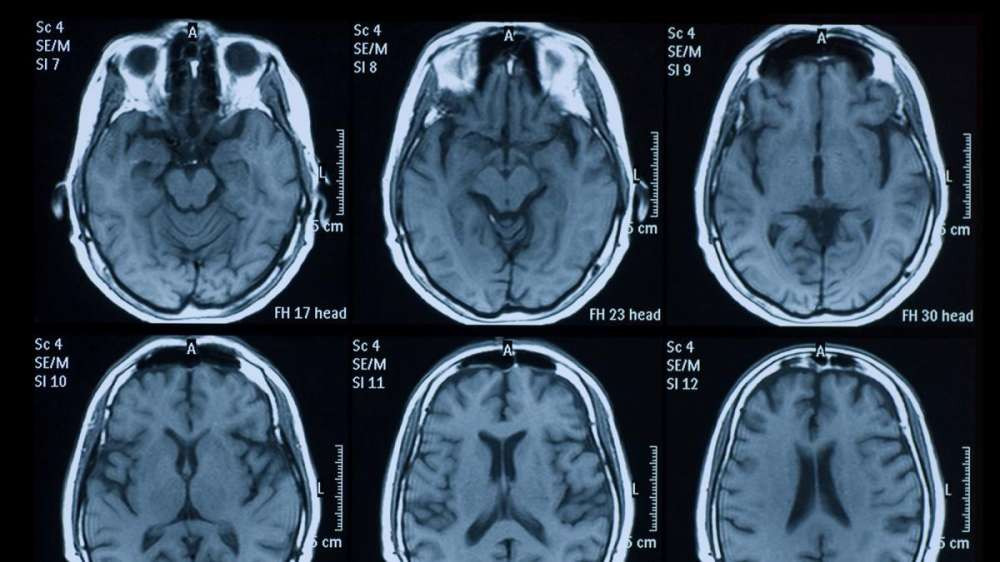

В других случаях исследования описывали тяжелый энцефалит у больного CоVID-19 (воспаление и отек головного мозга) и инсульт у здоровых молодых людей с легкими симптомами CОVID-19.

SARS-CoV-2, как полагают специалисты, может стать причиной появления неврологических расстройств. Это происходит либо непосредственно из-за заражения мозга, либо в результате чрезмерной реакции иммунной системы на коронавирус. Так, последние исследования смертельных случаев CОVID-19 выявили новый коронавирус в головном мозге зараженных. Также было высказано предположение о том, что инфекция обонятельных нейронов в носу может способствовать распространению вируса из дыхательных путей в головной мозг.

Клетки человеческого мозга экспрессируют белок ACE2 на своей поверхности. ACE2 – это белок, который участвует в регуляции кровяного давления и является рецептором, который вирус использует для проникновения и заражения клеток. Этот белок обнаружили на клетках эндотелия, выстилающих кровеносные сосуды и отвечающих за множество функций сосудистой системы. Зараженные клетки эндотелия могут позволить вирусу пройти из дыхательных путей в кровь, а затем в мозг, где размножение вирусных частиц может стать причиной появления неврологических симптомов.